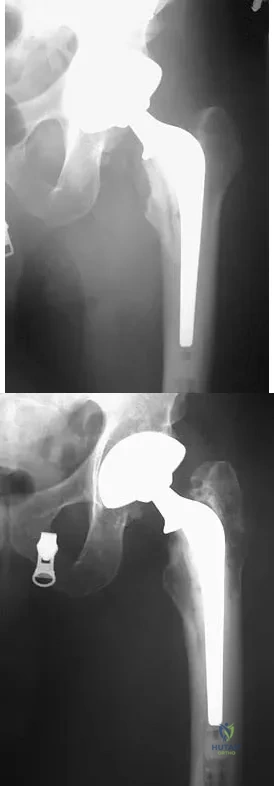

Figure 38 shows the radiograph of a 40-year-old woman who reports severe groin pain and lack of motion of the right hip. History reveals that the patient underwent a femoral osteotomy for hip dysplasia approximately 30 years ago. Treatment should include

Explanation

Although the patient is young, a total hip arthroplasty will provide pain relief and improve her range of motion. The arthritis is too advanced for the patient to benefit from an osteotomy. In addition, periacetabular osteotomy and hip arthrodesis do not improve range of motion of the hip. It has not been established that patients with severe osteoarthritis will benefit from arthroscopic debridement of the hip.